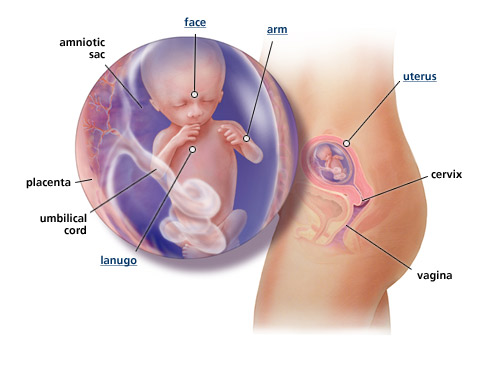

Saat Usg Trimester 2 Ibu Hamil Perlu Perhatikan 3 Hal Ini Info Sehat Klikdokter Com

Saat Usg Trimester 2 Ibu Hamil Perlu Perhatikan 3 Hal Ini Info Sehat Klikdokter Com

Ini Cara Membaca Hasil Usg Berdasarkan Jenisnya Jangan Bingung Lagi Ya Orami

Ini Cara Membaca Hasil Usg Berdasarkan Jenisnya Jangan Bingung Lagi Ya Orami